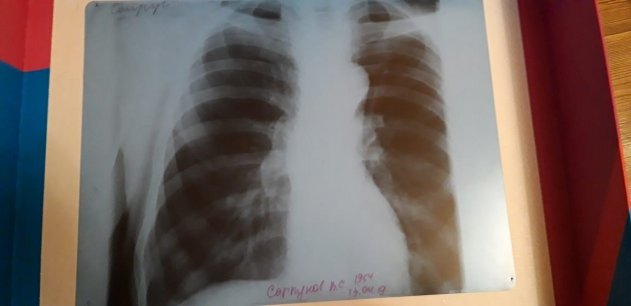

При этом, когда Василий Сапрунов был в больнице в Невьянске после того, как ему стало плохо на даче, там ему сделали снимок, на котором нет никакого протеза.

— Его спросили: а кто вам сказал, что у вас стоит эндопротез. Его изначально не было, сказали нам в больнице Невьянска, — говорит Сергей. — Получается, отец год промучился без этого эндопротеза, а мы при этом заплатили деньги за бесплатный протез.

На снимке, который сделали в больнице в Невьянске, протеза не видно